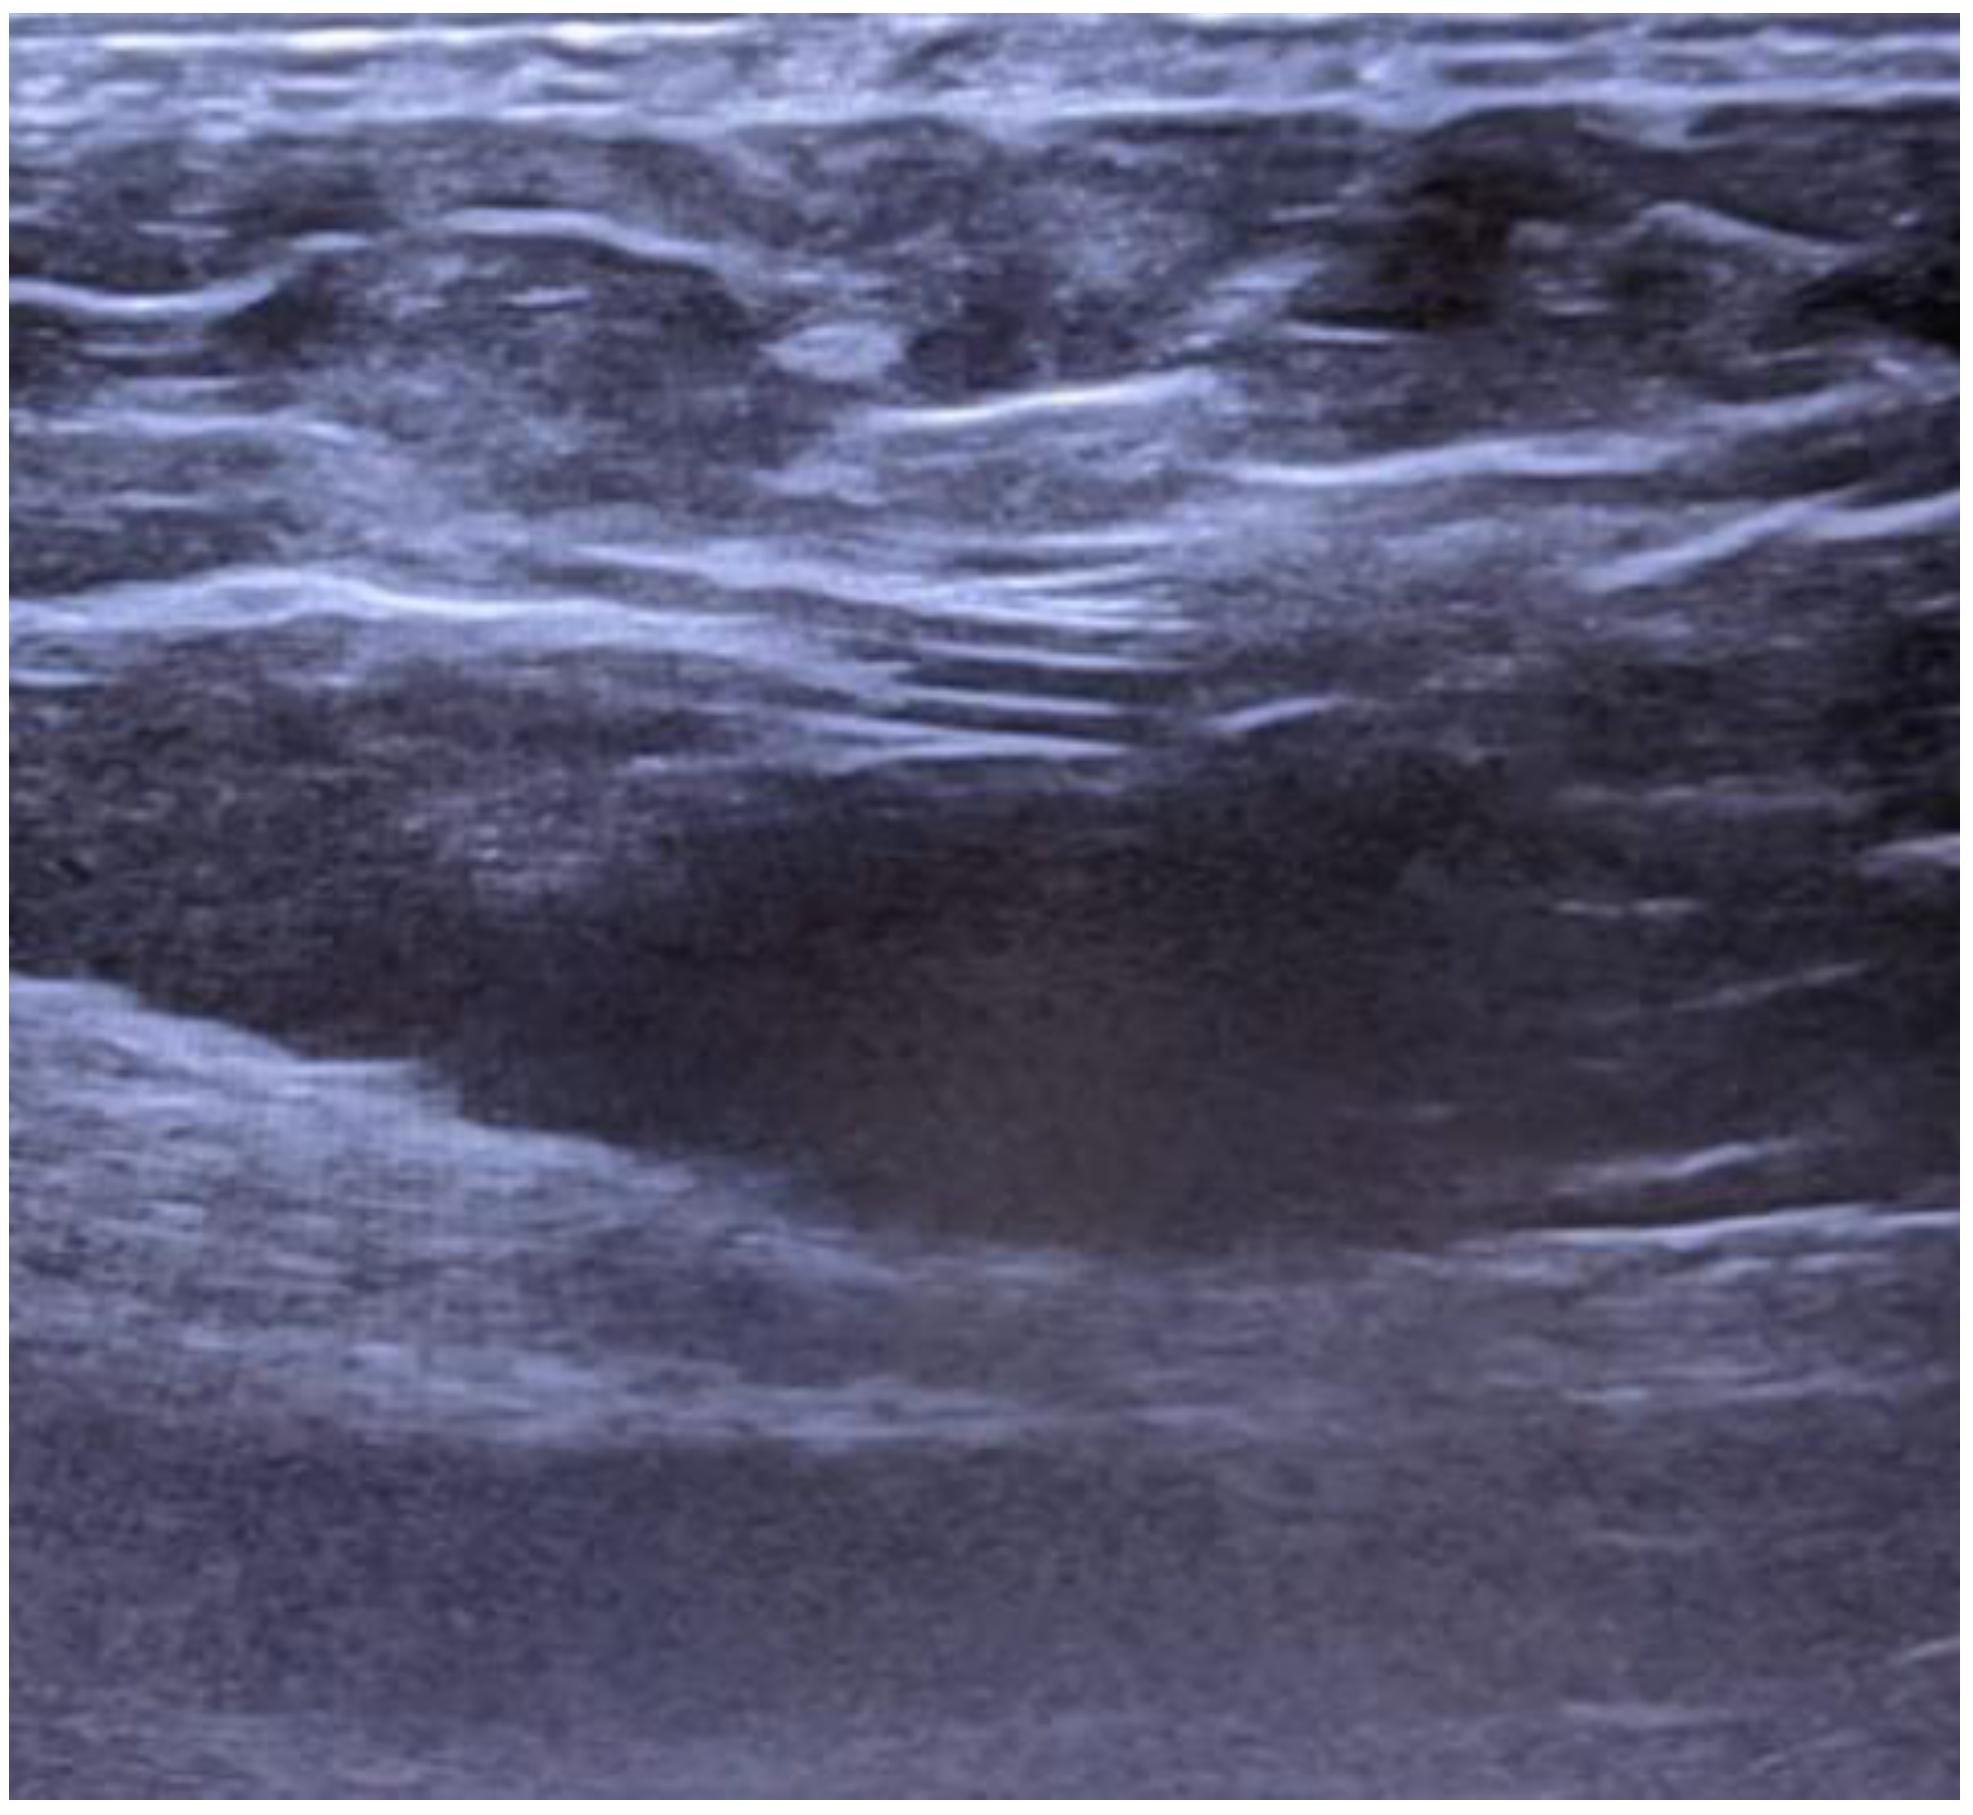

The ultrasound depicts the shunt as having a shallow trajectory from the right latero-cervical region to the epigastrium (Figure 3), from where it enters deeply, the access at the peritoneal cavity being located in the right paraumbilical area, but without being able to visualize the distal end (Figure 4). Neurosurgical consultation was subsequently performed, which recommended temporary shunt ligation. Suturing and ligation of the shunt was performed with the recommendation of ligature thread suppression 24 hours postoperatively and reassessment as needed.

Figure 4. Distal-end catheter entry in the peritoneal cavity